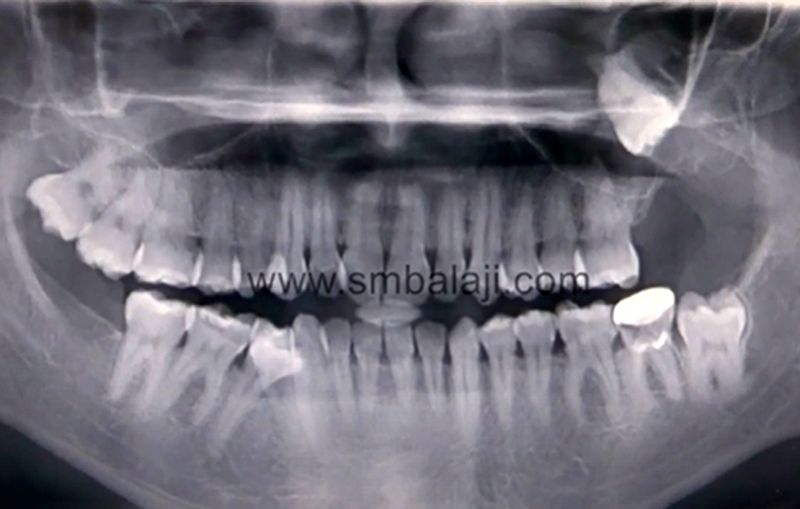

Follicular cyst and impacted lower wisdom tooth, extension

(A) Panoramic radiography a cystic lesion with wisdom tooth was seen What Is A Cyst Wisdom Tooth a dentigerous cyst is an odontogenic cyst (also known as a follicular cyst) that forms around the crown of an unerupted tooth, such as a wisdom tooth. It develops when fluid accumulates between the crown of. a dentigerous cyst is a smooth, round sack of clear fluid that slowly develops in the gums where an adult tooth is. What Is A Cyst Wisdom Tooth.

Follicular cyst and impacted lower wisdom tooth, extension What Is A Cyst Wisdom Tooth It develops when fluid accumulates between the crown of. a dentigerous cyst is a smooth, round sack of clear fluid that slowly develops in the gums where an adult tooth is coming in. a dentigerous cyst is an odontogenic cyst (also known as a follicular cyst) that forms around the crown of an unerupted tooth, such as a. What Is A Cyst Wisdom Tooth.

A panoramic xray of a mans jaw and teeth showing his impacted wisdom What Is A Cyst Wisdom Tooth what is a dentigerous cyst? wisdom tooth cyst is a serious issue that requires thorough treatment. a dentigerous cyst is an odontogenic cyst (also known as a follicular cyst) that forms around the crown of an unerupted tooth, such as a wisdom tooth. Cyst is a small sac filled with liquid that grows very. a dentigerous. What Is A Cyst Wisdom Tooth.